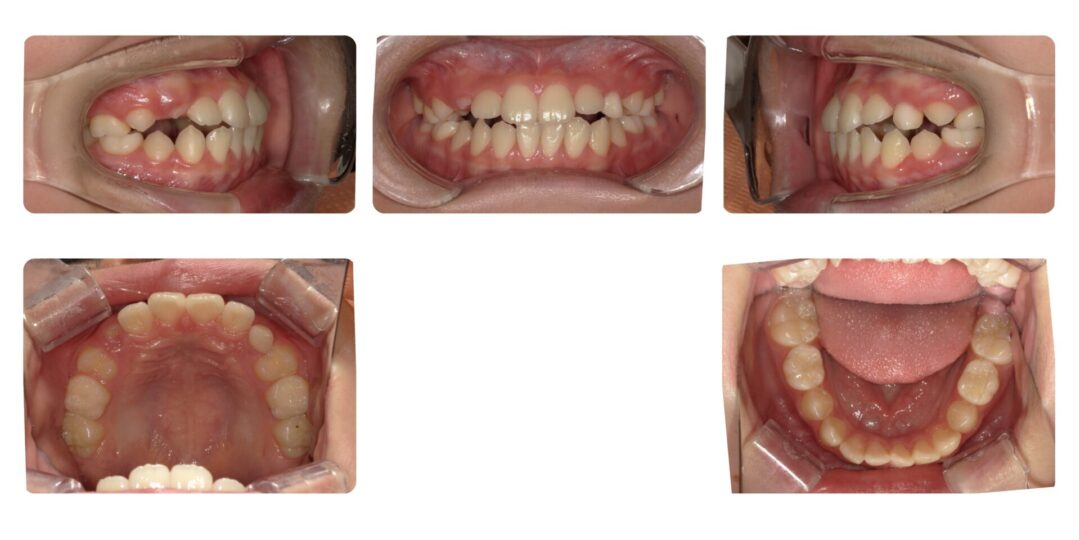

矯正治療後

第一期治療 上下拡大床(上顎タングガード付)

2年8ヶ月

自由診療 基本料金¥330,000 処置料¥3,300